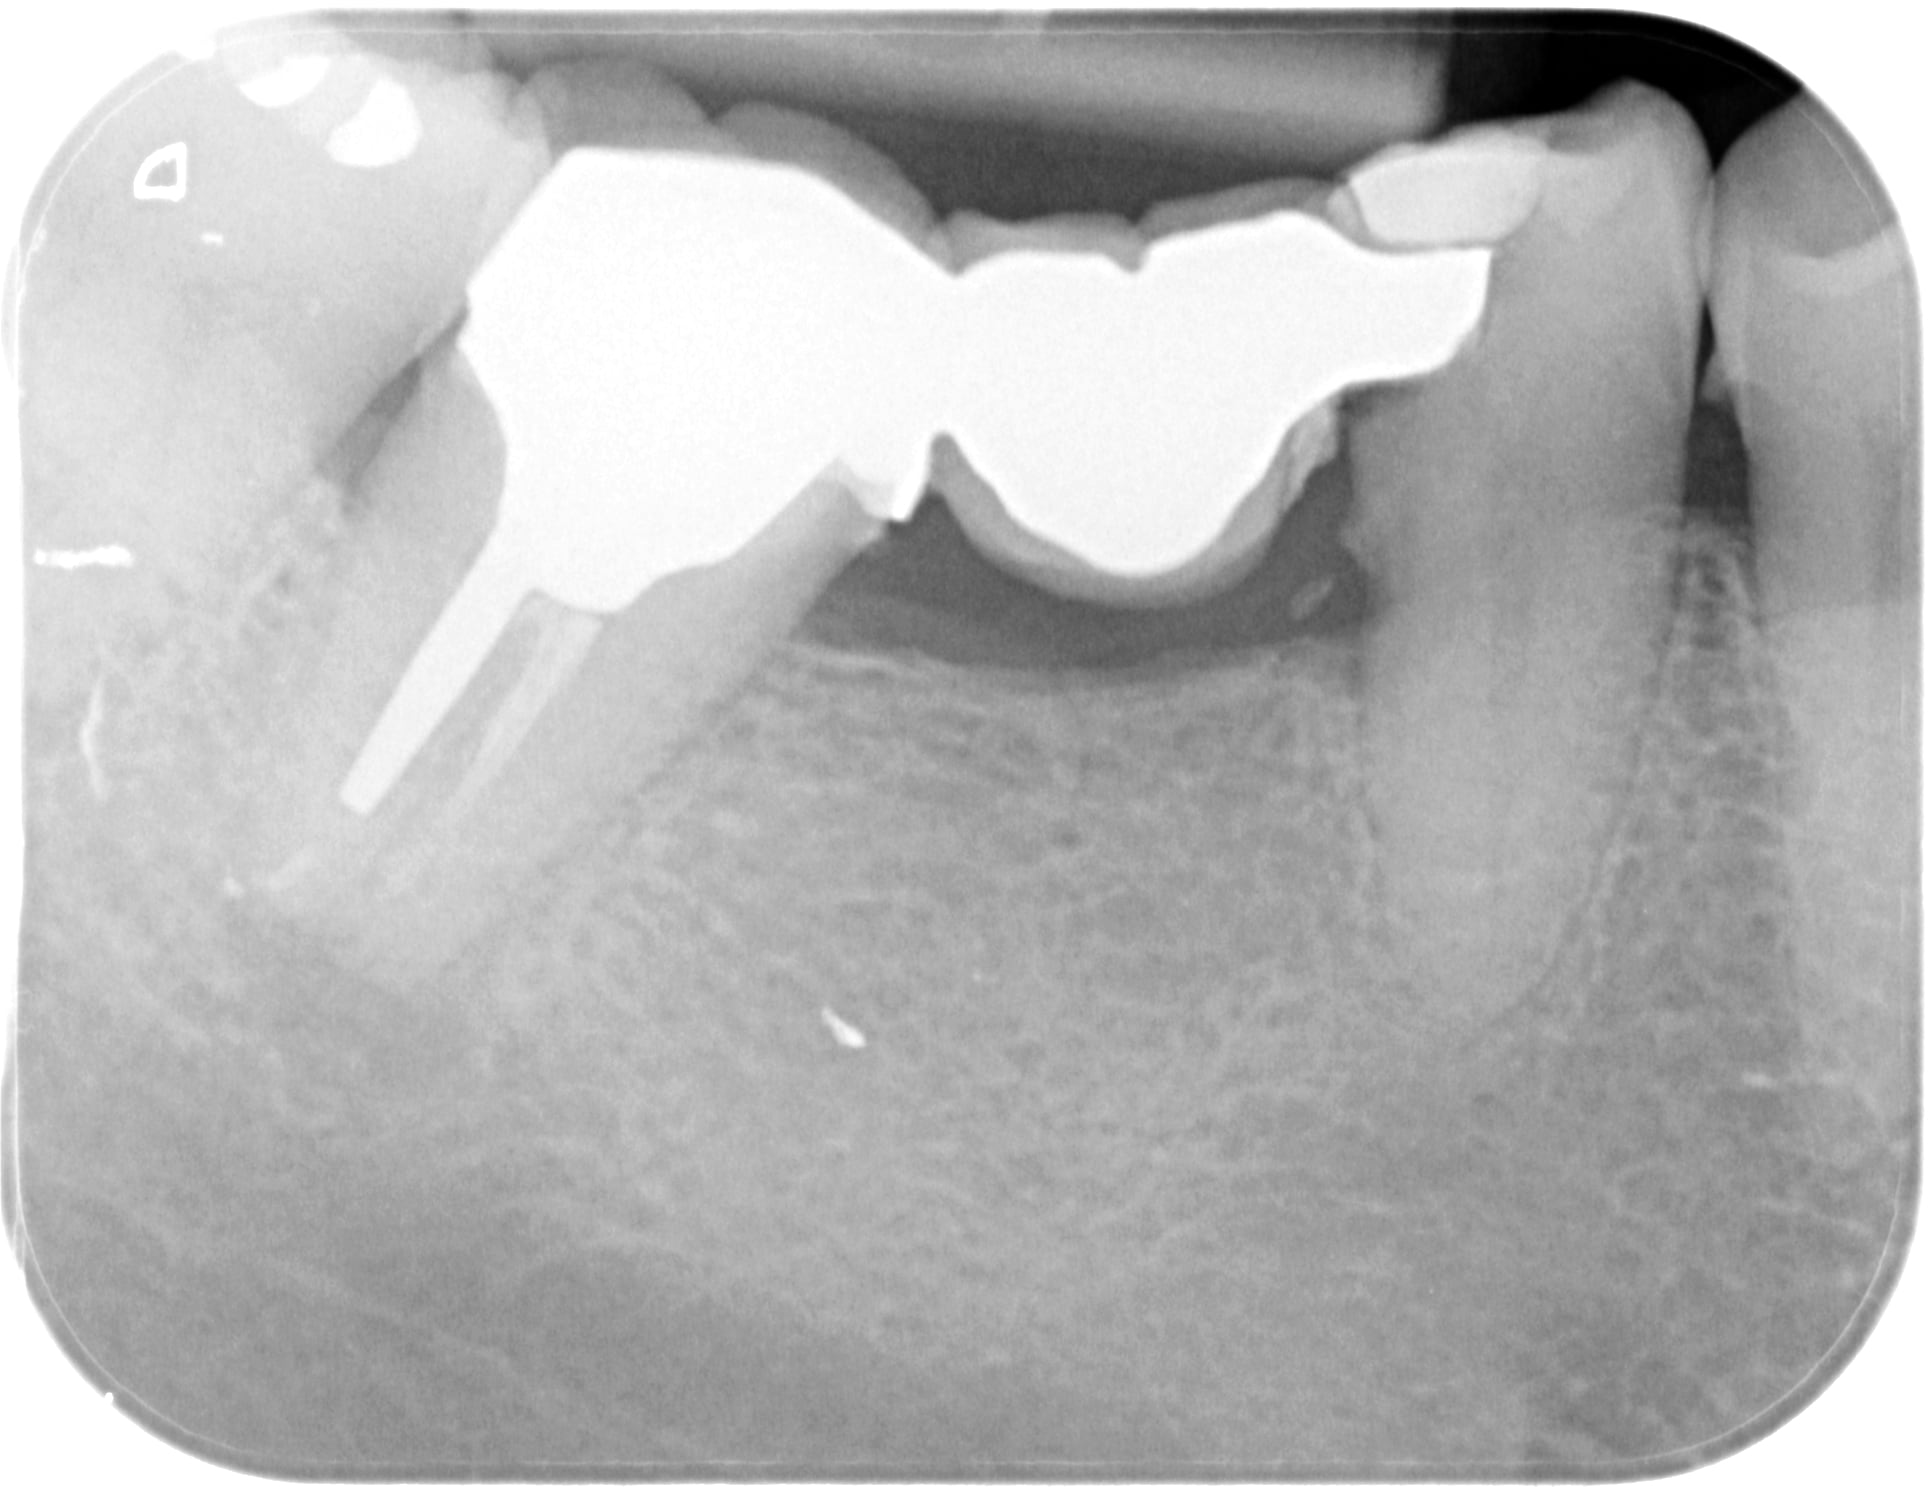

moi je fais tout bien mes controles... et c'est vrai que la priorité c'est la qualité des radios. (j'en ai des bien mieux mais je retrouve plus le dossier...)